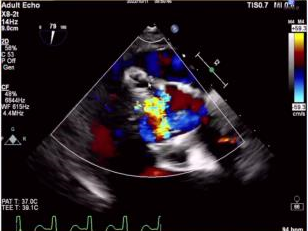

国际频道——中外理念与技术的碰撞

宋光远教授、Takashi Matsumoto教授、Hasan Jilaihawi教授、Moody Makar教授等中外专家云端荟聚,通过手术和学术讲座的形式就经导管二尖瓣缘对缘修复(TEER)进展,以及超声心动图在TEER和TMVR术中的应用,并就TEER失败时的诊疗策略,PASCAL在二尖瓣反流中的应用,TMVR在“瓣中瓣”和“环中瓣”应用所面临的挑战进行细致分析,并警醒临床医生当其他一切都失败时,要勇于跳出二尖瓣手术的条条框框,整体全面的看待问题。